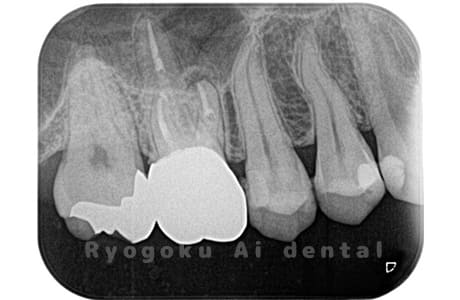

Case02

-

- 原因

- 慢性根尖性歯周炎

- 治療期間

- 3ヶ月

- 治療内容

- マイクロエンド

- 治療費用

- 121,000円

噛むと痛みが出る、とのことで来院した患者様です。他院での根管治療を終えてましたが、根尖病変を認めるため、マイクロエンドを行いました。